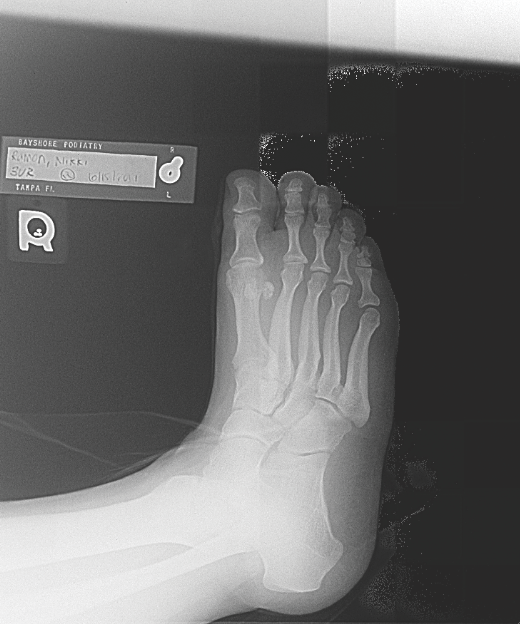

Stress fracture and skeletal bone injury after physical overuse outline Stress Fracture In Athletes Stress fractures of the foot and ankle are common injuries in athletes. Around 0.8% of high school athletes sustained a stress fracture [2]. A stress fracture is a partial or complete bone fracture that results from repeated application of stress lower than the stress required to fracture. Stress fractures can affect every sporty person, from weekend athletes to top athletes.. Stress Fracture In Athletes.

Stress fractures of the foot, let's discuss the facts... Stress Stress Fracture In Athletes Stress fractures are common in. A stress fracture is a partial or complete bone fracture that results from repeated application of stress lower than the stress required to fracture. Bone stress injuries (bsi) encompass a spectrum characterized by an imbalance in bone tissue caused by repetitive. Revised and expanded second edition covering the presentation, diagnosis and management of stress fractures. Stress Fracture In Athletes.